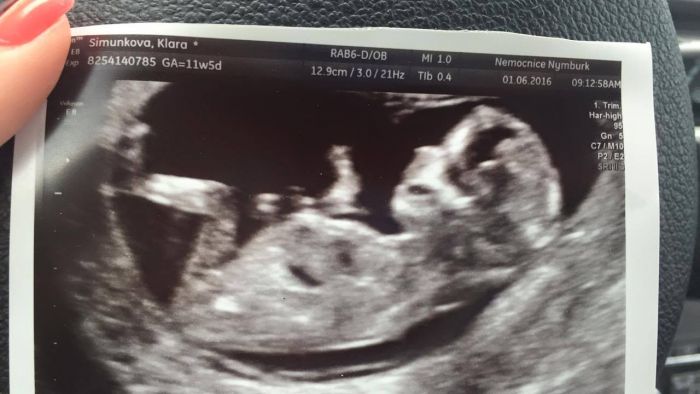

Autor: Klára34 2.6.2016 v 07:27

Ahoj holky...Tak je to za mnou...Termín upraven na 11.12. Dnes Tedy 12+5.Normálně jsem se tam málem rozbrečela...to byla prostě bomba

Jo a zapoměla jsem dodat:Asi je to zase holka...doktorka řekla že se dobře ukazuje že to vidí tak na 70%

Klarko, moc krasny fotecky a mozna dalsi holcicka, gratuluju